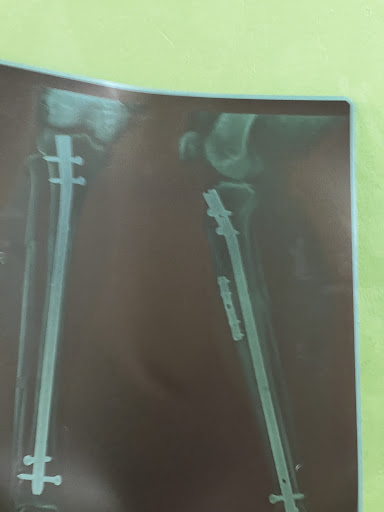

Dr. Satish Prasad Barnawal is a highly reputed orthopedic surgeon in Kathmandu, Nepal, known for his top-tier expertise, compassionate care, and outstanding surgical outcomes. With extensive experience in managing complex orthopedic conditions, he has earned a reputation as one of the best orthopedic doctors in Nepal, attracting a high patient flow from across the country and abroad.

Dr. Satish Prasad Barnawal has 6 years of extensive experience in Orthopedics at B & B Hospital, Lalitpur, Nepal, one of the country’s leading centers for trauma and bone & joint care. He has been actively involved in managing a wide range of cases including fractures, dislocations, polytrauma, and complex orthopedic injuries. His expertise covers…